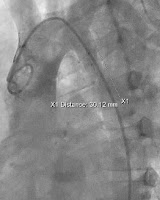

Burada ağır bir Aort koarktasyonun’da işlem öncesi ve sonrası görüntüler izlenmektedir.